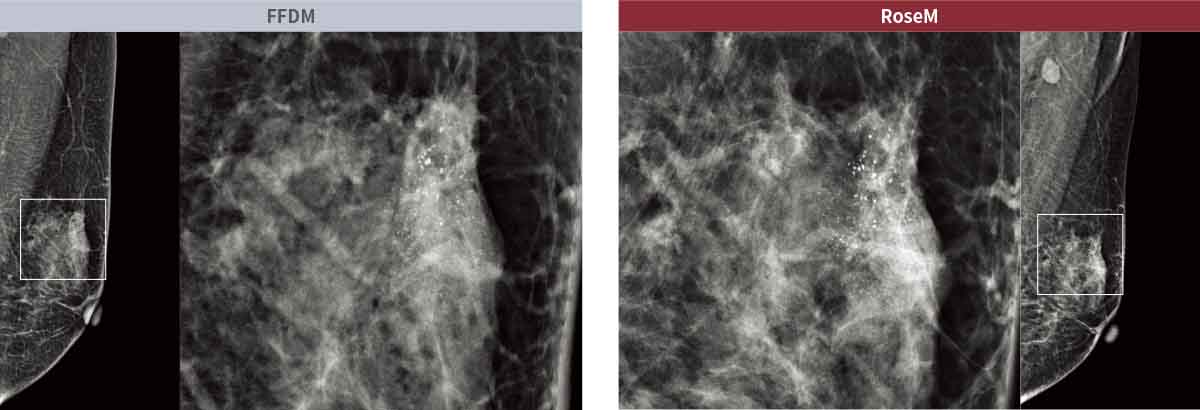

- Imagens de Alta Qualidade para Detecção Precoce do Cancro da Mama